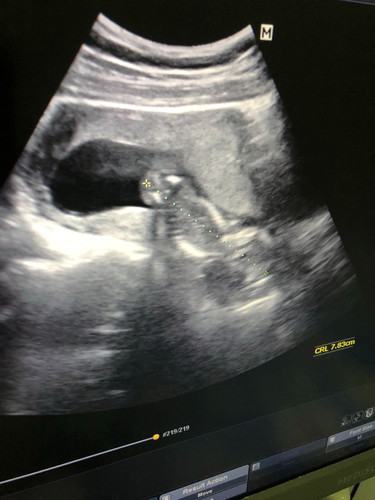

ซาวด์มาลูกอยู่ผิดตำแหน่ง ซาวด์ครั้งก่อนตำแหน่งปกติ ใครเคยเป็นบ้างคะ หมอบอกมีภาวะเสี่ยงแท้งได้ แต่ไม่ปวดท้องไม่มีเลือดไหล ตอนนี้ 14 weeks กังวลมากเรยคะ ?